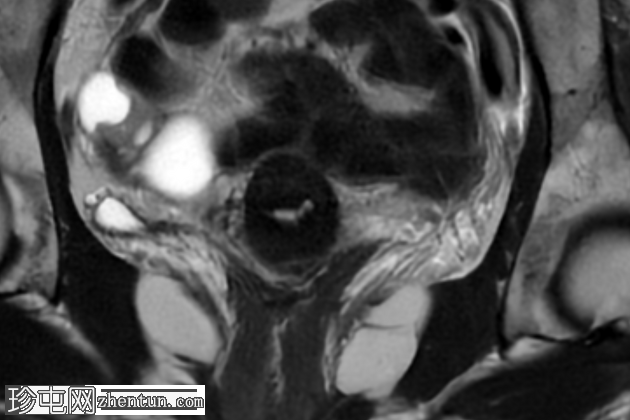

冠状位

T2加权像

盆腔MRI显示右侧卵巢解剖位置可见一边界清晰的卵圆形肿块。该病灶由囊性和实性成分组成。囊性部分壁薄,在T2加权像上呈均匀高信号,在T1加权脂肪抑制序列上呈低信号,无对比剂增强。该实性成分的信号特征与正常卵巢组织相似,DWI成像未见扩散受限,静脉注射造影剂后未见异常强化。

此外,在子宫左侧壁可见一管状薄壁囊性结构,延伸至同侧髂外血管,末端呈盲端。该结构在T2加权像上呈均匀高信号,在T1加权脂肪抑制序列上呈低信号,且无造影剂强化。

本例中,盆腔MRI显示,患者右侧卵巢解剖位置存在一个边界清晰的附件肿块,该患者有20年前行双侧输卵管卵巢切除术的病史。该病灶包含囊性和实性成分,其中实性部分表现出与正常卵巢组织相似的信号特征。无扩散受限和无可疑的增强扫描强化提示排除恶性病变。这些影像学特征结合相关的手术史进行解读,符合残留卵巢组织的特征,支持卵巢残留综合征的诊断。此外,还发现对侧子宫左侧延伸出一个管状薄壁囊性结构,末端呈盲端。其形态、信号特征和无强化表现符合输卵管残端或输卵管残端积水,这是输卵管切除术后常见的术后表现。附件残余的存在进一步支持术后病因,而非原发性妇科肿瘤